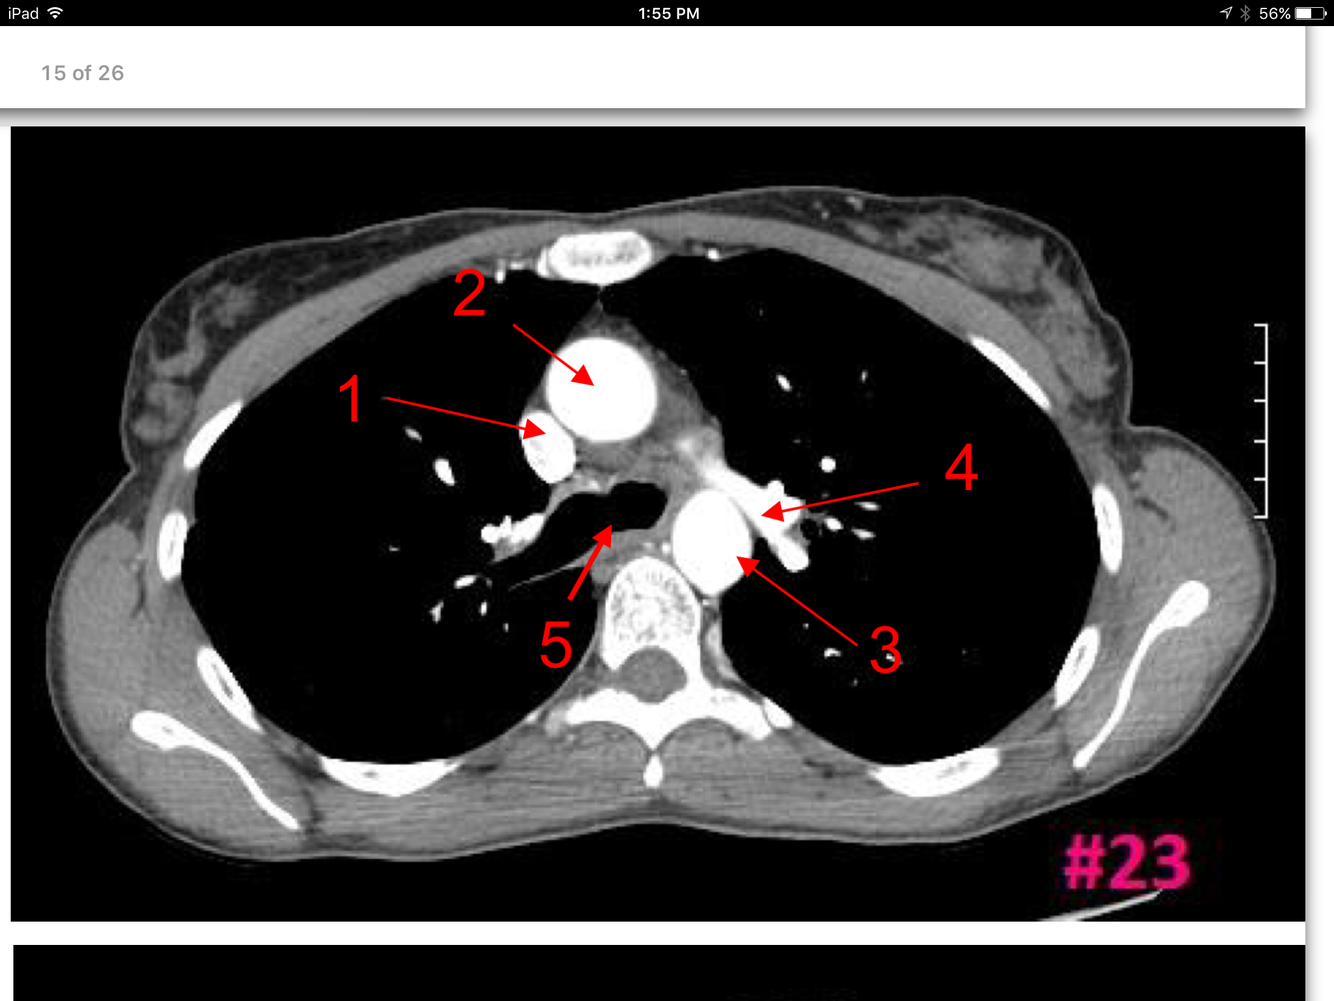

15

Q

A

Superior vena cava

Ascending aorta

Descending aorta

Lt pulmonary artery

Lt main bronchus

Rt main bronchus

Rt pulmonary artery

Rt intervertebral foramen